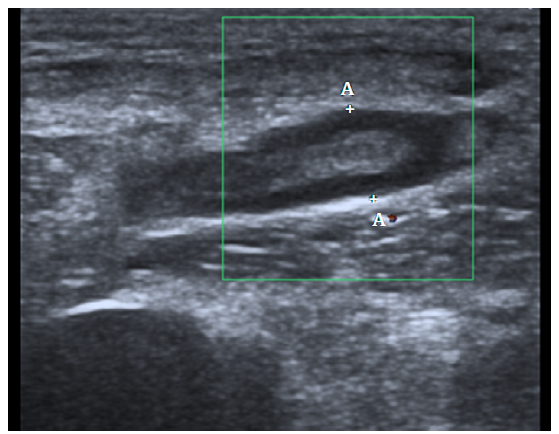

Figure 2 Ultrasound of the inguinal region. 2a) thickening of the tip of the appendix; 2b) fluid with thin septa inside the hernia sac. Arrow: compression of the medial wall of the femoral vein: AF, superficial femoral artery; AP: deep femoral artery; VP, deep femoral vein.

Based on the findings of the physical examination and the initial ultrasound, it was decided to hospitalize the patient and perform a series of pre-surgical laboratory tests, all of which were within normal ranges. An ultrasound study was performed again, confirming the presence of a De Garengeot hernia and showing that the vermiform appendix had a thickening in the walls of its tip, with an anteroposterior diameter of 6.7mm that did not decrease with external pressure, as well as scarce free fluid in the hernia sac (Figure 3).